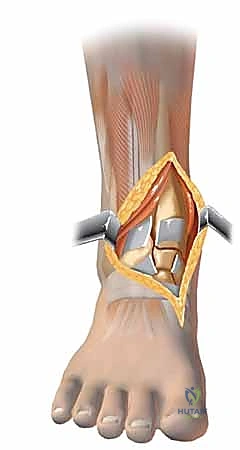

الخطوات الجراحية التفصيلية: إبداع التثبيت الداخلي المفتوح (ORIF)

في صنعاء، يطبق الأستاذ الدكتور محمد هطيف المبادئ الأربعة الكلاسيكية التي وضعها (Ruëdi and Allgöwer) والتي تم تحديثها بالتقنيات الحديثة، وتتمثل أهدافها في:

1. إعادة بناء مفصلية دقيقة (Anatomic Articular Reduction): لا مجال للخطأ هنا. يجب إعادة بناء السطح المفصلي بدقة المليمتر لتجنب احتكاك الغضاريف وحدوث خشونة مبكرة.

2. استعادة طول الطرف ومحاذاته (Restoration of Length and Alignment): لمنع العرج وتوزيع الوزن بشكل غير متساوٍ على الركبة والورك.

3. التطعيم العظمي (Bone Grafting): لملء الفراغات الناتجة عن انضغاط العظم الإسفنجي.

4. تثبيت الكسر المستقر (Stable Fixation): باستخدام شرائح ومسامير متطورة للسماح بالحركة المبكرة للمفصل.